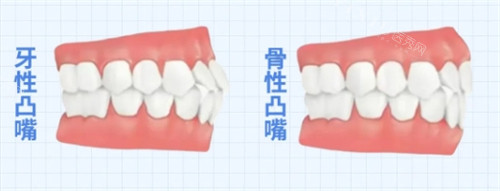

一、什么是骨性嘴凸?

骨性嘴凸主要表现为上颌前突或下颌后缩,导致嘴唇无法自然闭合。与单纯牙齿不齐不同,这种问题涉及颌骨发育异常,需要早期干预才能取得理想结果。